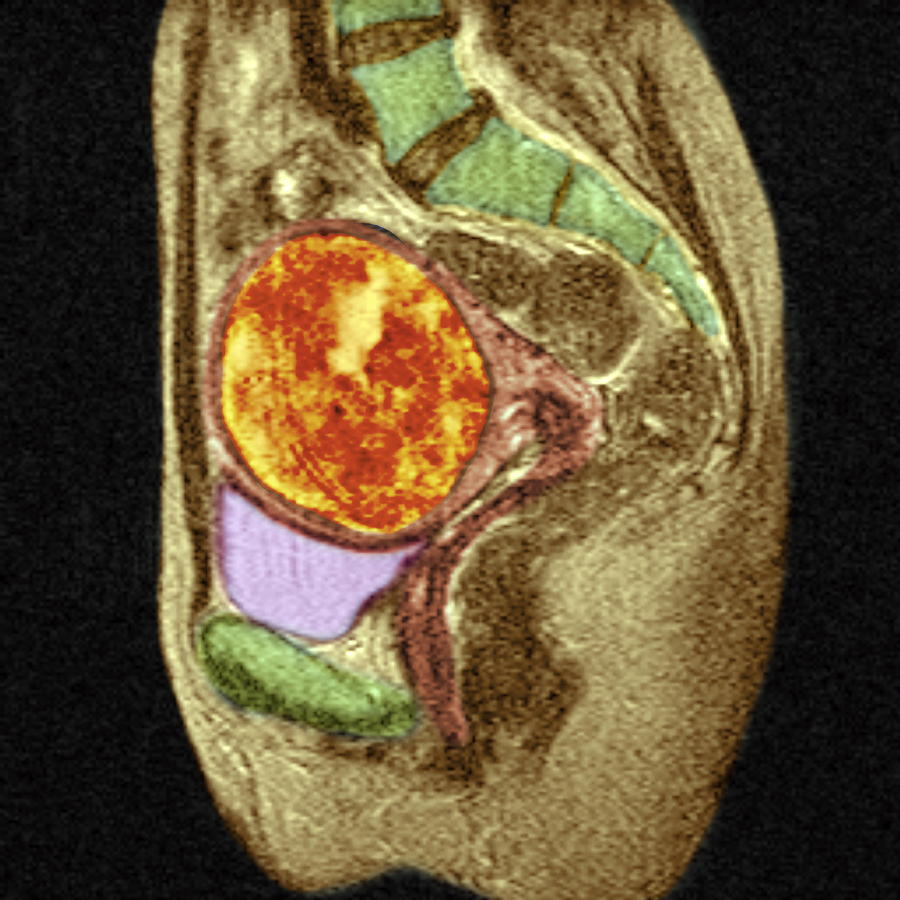

MRI pelvis of a large posterior wall fibroid with cystic degeneration …

Uterine Fibroid, Mri Scan Photograph by Du Cane Medical Imaging Ltd

Pelvic MRI for Fibroids – Why You Need an MRI to Detect Fibroids

Uterine Fibroid, Mri Scan Photograph by Du Cane Medical Imaging Ltd